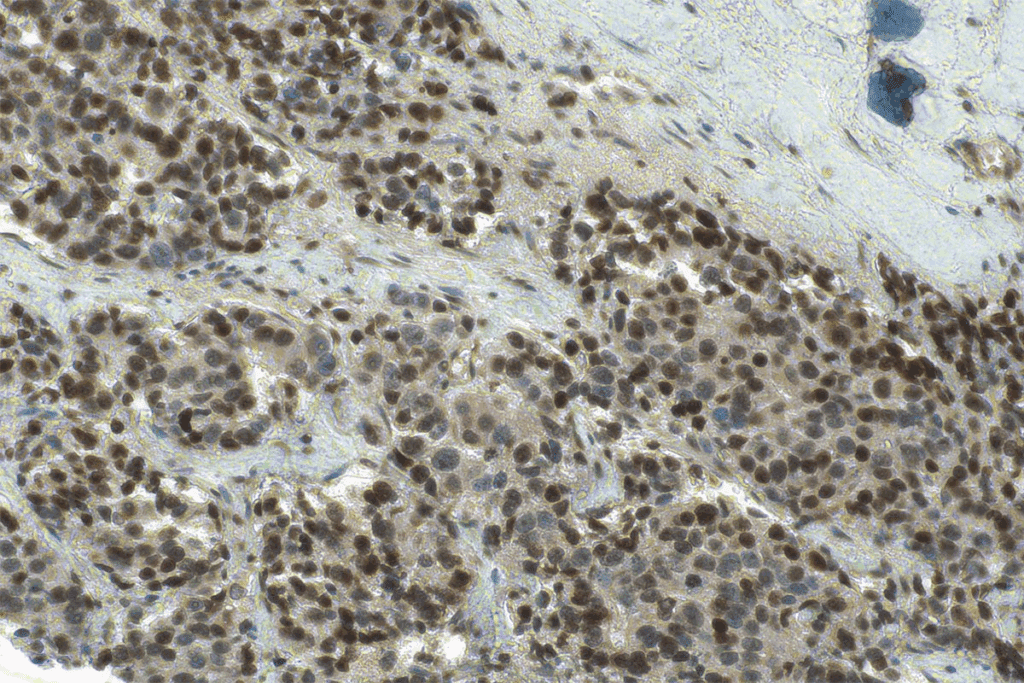

Under a microscope, CIS cells show distinct features. Their structure is disorganized, unlike normal cells. This disorganization is a sign of abnormal growth in CIS.

| CIS Cells | Disorganized | Present | No Stromal Invasion |

CIS cells look abnormal under a microscope. They have unique features that show they’re not normal cells. But, they don’t invade the surrounding stroma.